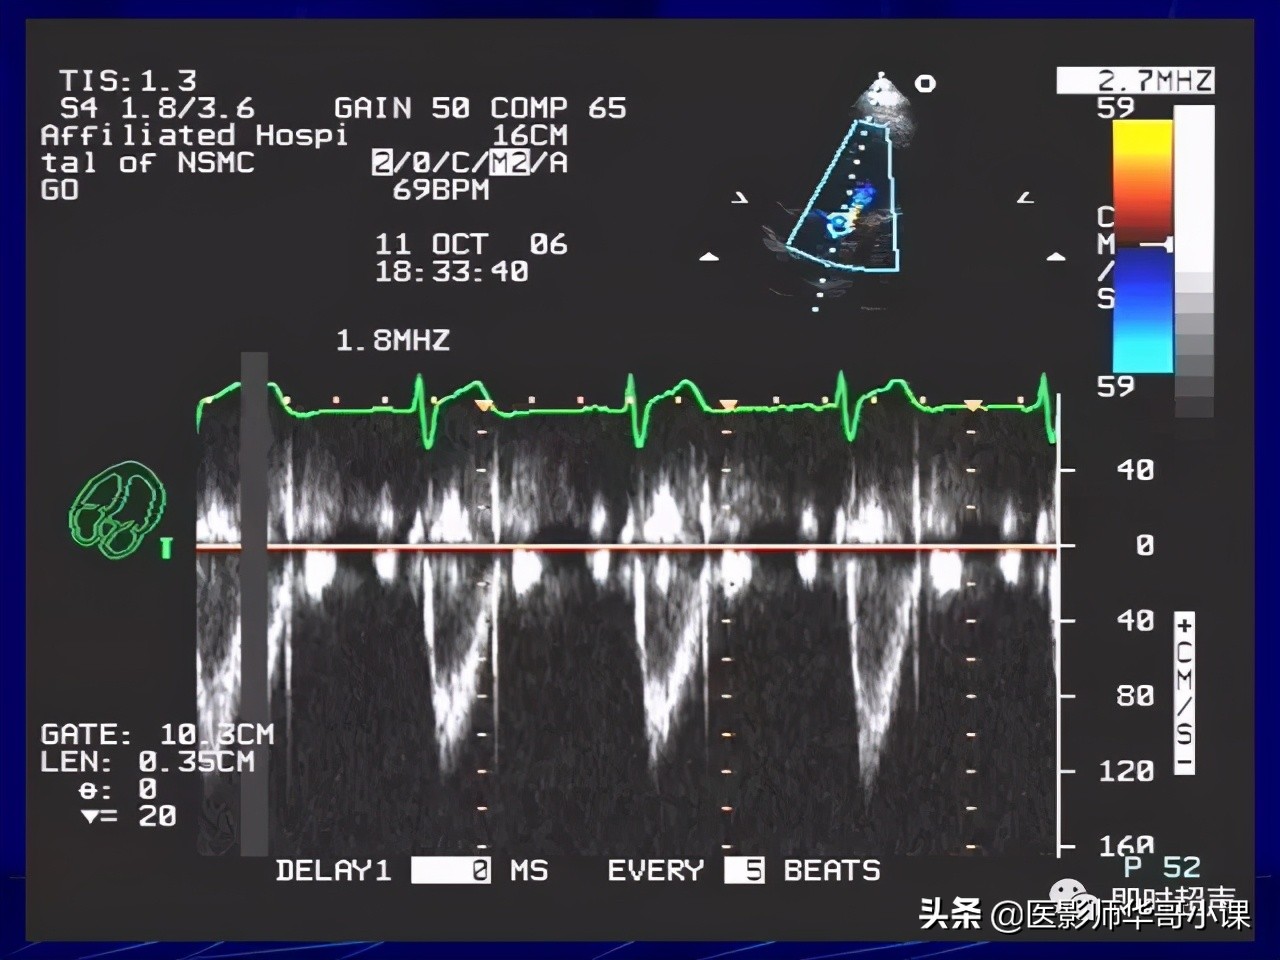

超声检查软指标课件 (超声诊断最新课件)

超声检查报告单讲解,超声图像检查